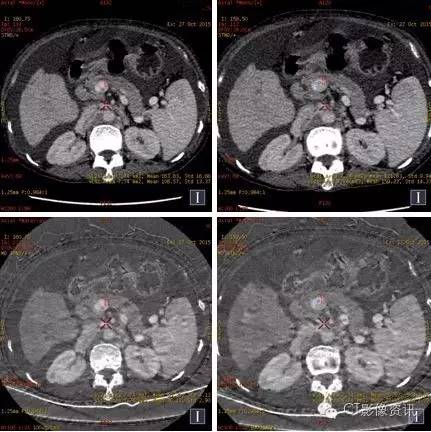

病例资料 女性,51岁,食欲下降5个月,上腹不适3个月。

碘基图像对肝脏结节的血供显示更敏感,碘基图上我们可以看到更多清晰的小病灶。

分别测量并计算正常肝脏及病灶在动脉期及门脉期的肝动脉碘分数(注1)及门脉碘含量(注2),结果见下表。

AIF肝脏=5.51/18.53=0.3;PVIC肝脏=18.53-5.51=13.02 AIF病灶=35.65/23.92=1.5;PVIC病灶=23.92-35.65=-11.73

注: 1、肝动脉碘分数AIF(ArterialIodine Fraction)=碘含量(动脉期)/碘含量(门静脉期) 2、门静脉碘含量PVIC(Portal VenousIodine Concentration)=碘含量(门静脉期)-碘含量(动脉期)